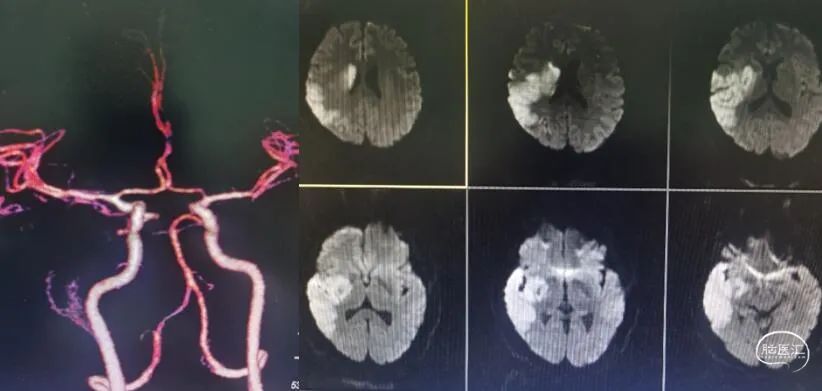

术前多模CT:右侧颈内动脉无嫌疑;CT平扫:大脑中动脉高密度帧,颞叶、岛叶脑沟、脑回灰质、白质分界不清;多模CT评估:缺血半暗带约198ml。

造影可见:颈内动脉起始部闭塞。

术中使用90cm NeuronMax、 125cm多功能管及泥鳅导丝,但NeuronMax无法通过闭塞段,远端可见继发长节段血栓。

随后选择Sterling3×30 8atm的球囊通过血管进行球囊扩张。选用中间导管进行抽吸,再通过微导管、微导丝进入大脑中动脉,进行持续抽吸,抽吸出长节段血栓。随后近端可见充盈缺损,将保护伞回收,回收血栓后重新植入保护伞。随后进行球囊扩张及支架成型。

(使用Wallstent 9/30)

出院时:NIHSS 5分,神志清楚,面瘫+左侧肢体肌力3级。